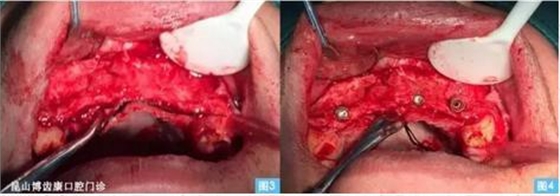

圖3圖4:(左圖3)牙槽嵴頂偏腭側(cè)水平切口,雙側(cè)附加切口翻開(kāi)全厚粘骨膜瓣至鼻底,清晰暴露術(shù)區(qū)。(右圖4)小球鉆定位,擴(kuò)孔鉆依次備洞,植入植體 ,可見(jiàn)13、23唇側(cè)骨壁缺損嚴(yán)重 。